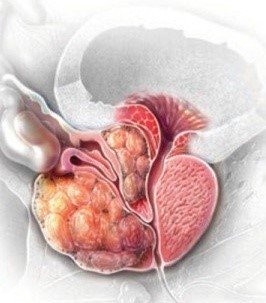

- 소변에 피가 섞여 나옴 (혈뇨)

- 설명: 암이 진행되어 요도나 방광 경부를 침범했을 경우 소변에 피가 섞여 나오는 혈뇨가 나타날 수 있습니다. 하지만 이는 암이 어느 정도 진행된 후 나타날 수도 있고, 방광염이나 요로결석 등 다른 질환으로도 발생할 수 있습니다.

전립선암 초기증상 - 정액에 피가 섞여 나옴 (혈정액증)

- 설명: 전립선은 정액의 일부를 만드는 기관이기 때문에, 암세포가 정낭 등을 침범하게 되면 사정 시 정액에 피가 섞여 나오는 증상이 나타날 수 있습니다.